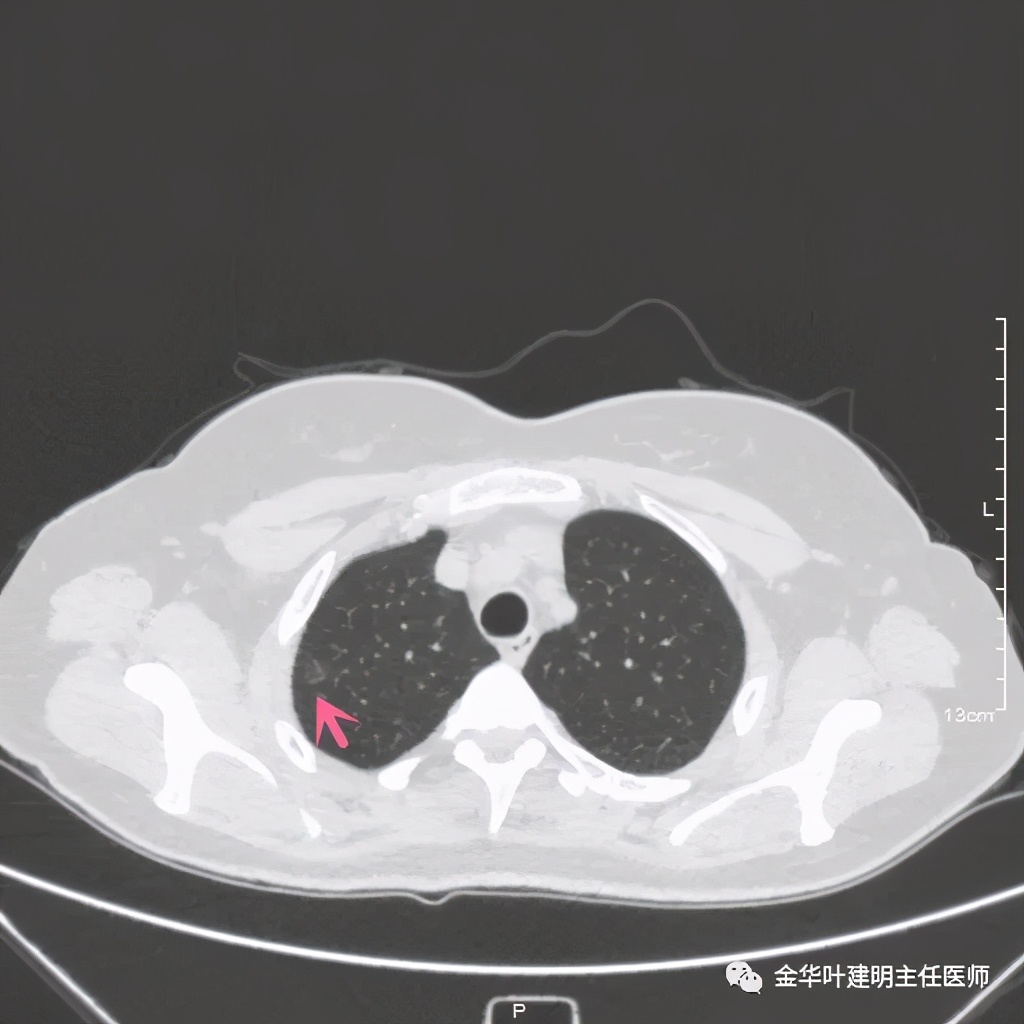

患者女性,50岁,检查发现右上肺结节已经近5年,我对比了其主病灶,密度略有增大,病灶看上去更清楚了,个人以为应该是微浸润性腺癌可能性较大,另有一次病灶,密度低,考虑腺瘤样不典型增生可能性大。我们先来看病灶:

上图示病灶1

靶扫描示明显血管进入病灶

从位置来看应该都是在尖段

尖段:因动图只能插入一次,所以尖段与后段的动图无法展示,我们选取最佳层面进行标注相关的亚段支气管:

因为横断面的关系,红色箭头示尖段支气管的开口,绿色箭头示后段支气管